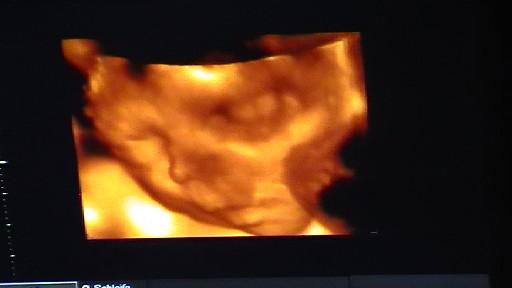

@Vroni: bin ja schon so gespannt auf deinen Ultraschall..... aber das dauert ja leider noch....

08/14 5. ICSI 2x 4 Zeller/ 3 auf Eis/ positiv HCG 402/ 1. US: Überstimu & Dottersack zu weit unten 2. US: alles im Grünen! welch Erleichterung!, 3.US: Herz flimmert, Embryo etwas kleiner...wir hoffen, dass es sich gesund weiterentwickelt..4.US: zu klein, kein Herzschlag, Montag AS wegen MA 9.SSW- ich versteh die Welt nicht mehr

Kryo-2 Blastos/ positiv, 1.us keine fruchthülle, hcg steigt nicht richtig, 😱 2.US nichts-wert schlecht: FG

kryo:11/2016:2 Blastos/positiv: 1US: zu kleine fruchthülle, hcg nur 180...:FG